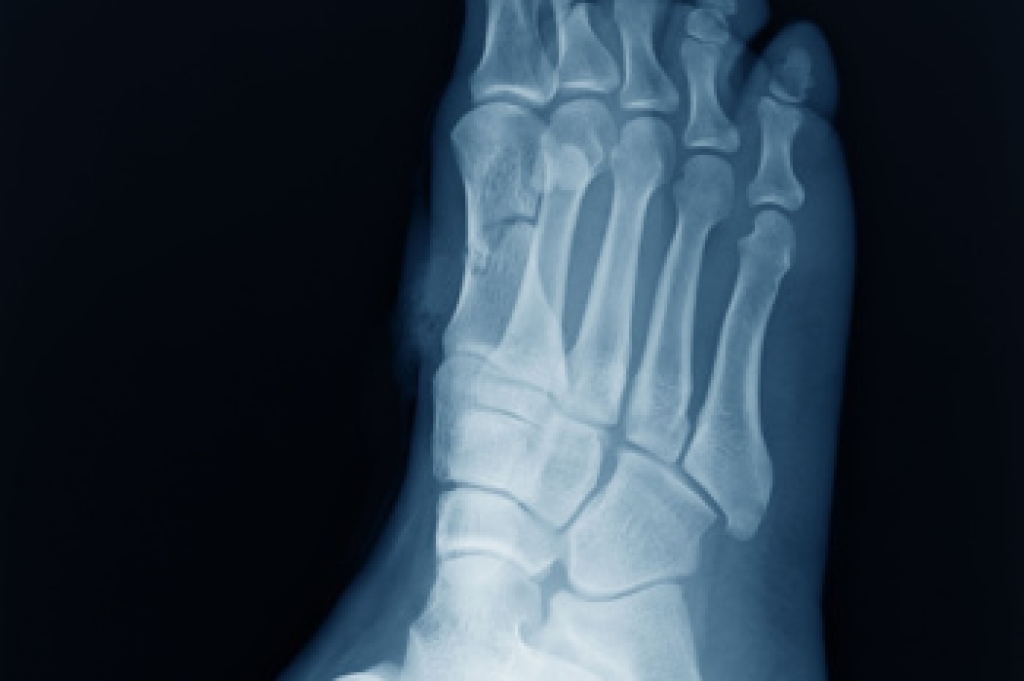

The most common injuries that occur in sporting activities include:

- Broken Foot

- Stress Fractures